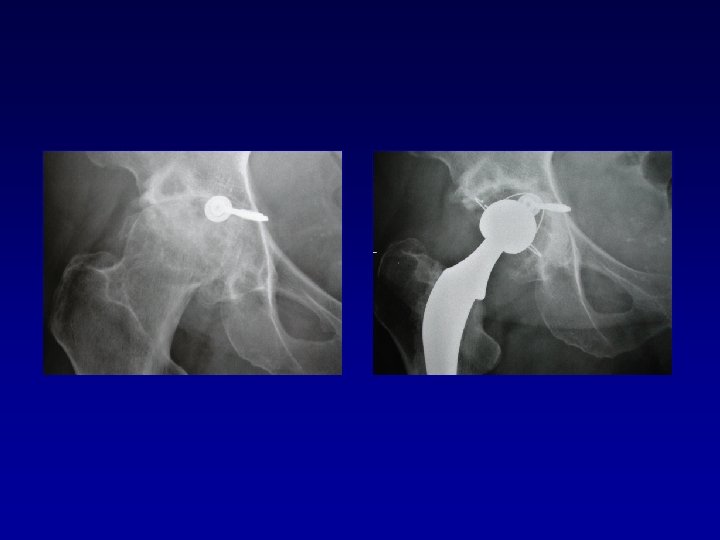

Arthroplastie totale de hanche sur fracture du cotyle complexe (LCH) • Voie d’abord par

Arthroplastie totale de hanche sur fracture du cotyle complexe (LCH) • Voie d’abord par TROCHANTEROTOMIE Libération de la fibrose, capsule, cicatrices • Permet : Exposition Récupération de la longueur Mobilité

Arthroplastie totale de hanche sur fracture du cotyle complexe Recentrage, reconstruction, orientation du cotyle

Arthroplastie totale de hanche sur fracture du cotyle complexe Recentrage, reconstruction, orientation du cotyle • • Greffe Ostéosynthèse par plaque MK Surtout si pseudarthrose Réduction de la luxation